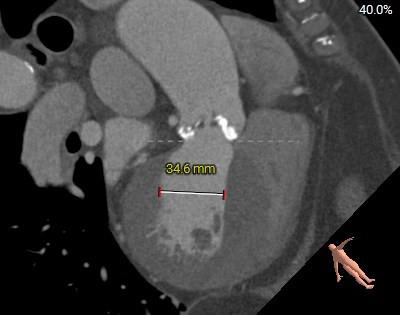

主动脉根部测量

瓣环角度及弓角弓距

◇ 主动脉瓣环水平夹角52°,非横位心,主动脉弓角度较锐(43°)及弓距偏短;